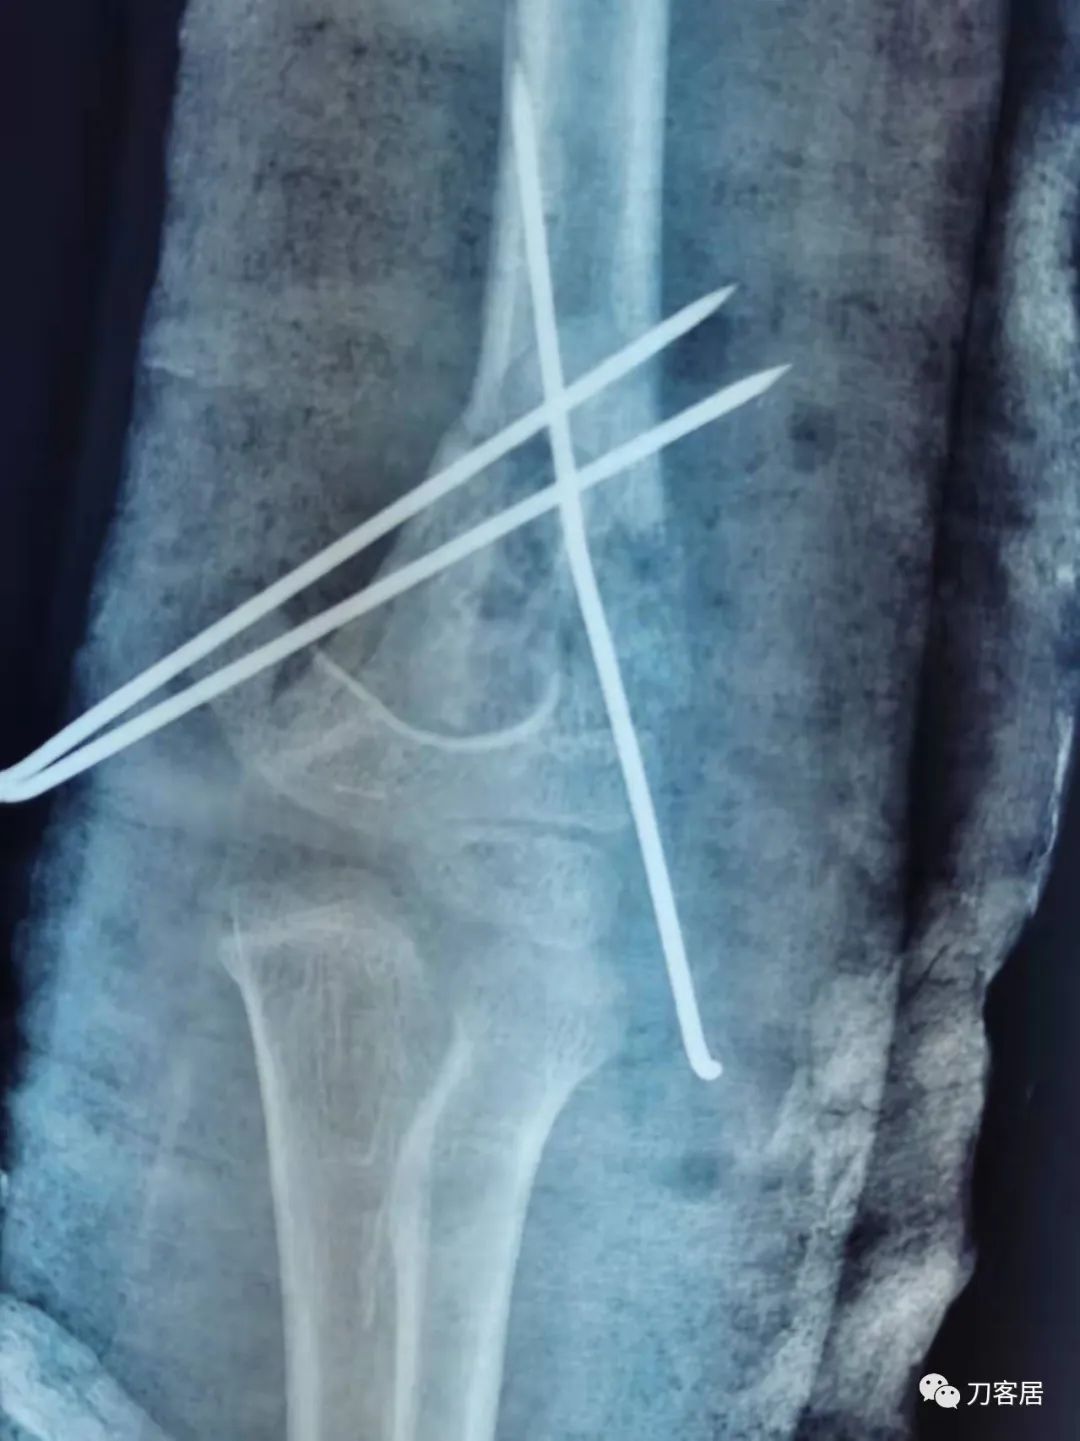

当地省中医院术后正位X线片

当地省中医院术后侧位X线片

患者术后病情平稳,拍片复查示骨折对位对线良好,内固定在位。外固定稳妥。于2021年9月29日出院。